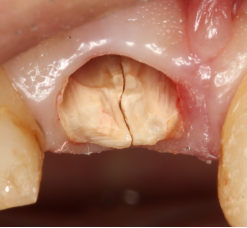

前歯が割れてしまってインプラントをご希望で来院された患者様です。

前歯に亀裂が入ってしまっており、抜歯後、インプラント治療を行いました。

非常に審美的な治療が出来ました。

当院では難しい前歯のインプラントも違和感なくきれいに処置することが出来ます。